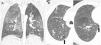

Expiratory CT scan is a complementary technique of inspiratory CT that provide valuable physiological information and may be more sensitive to detect air trapping than pul-monary function tests. It is useful in many obstructive airway diseases, including obliterative bronchiolitis, asthma, Swyer-James syndrome, tracheomalacia, hypersensitivity pneumonitis and sarcoidosis. In obliterative bronchiolitis, expiratory CT scan may be the only imaging technique that shows abnormalities in the early phase of disease. In order to obtain a good quality study, we should explain the procedure to the patient, use precise instructions and do some practice before image acquisition. Here we describe strategies to optimize the techni-que and propose an algorithm that help in interpretation of imaging findings in patients with obstructive airway disease.